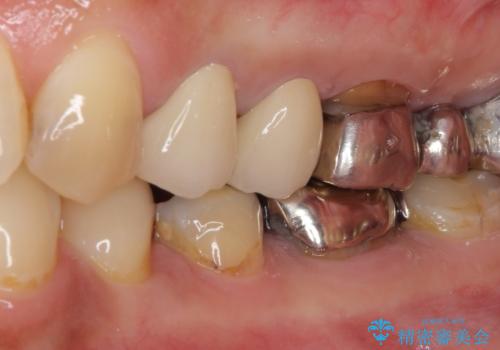

- 歯肉が退縮したためにクラウンの縁や歯根が見えてしまっていることを気にして来院された患者様です。

仮歯に変えた後にオールセラミッククラウンにて補綴することとしました。

強い咬合力や磨きすぎなどにより、歯根が見えてしまったり、金属の縁が見えてしまったりし、審美障害を引き起こすことがあります。

歯根が変色してしまうと、歯肉越しに歯根の黒い色が透けてしまうことがあり、この点についてはどうにも施しようがないため、患者様には事前のご理解いただきました。

治療前と比べてとても自然な前歯となり、患者様には大変満足していただきました。